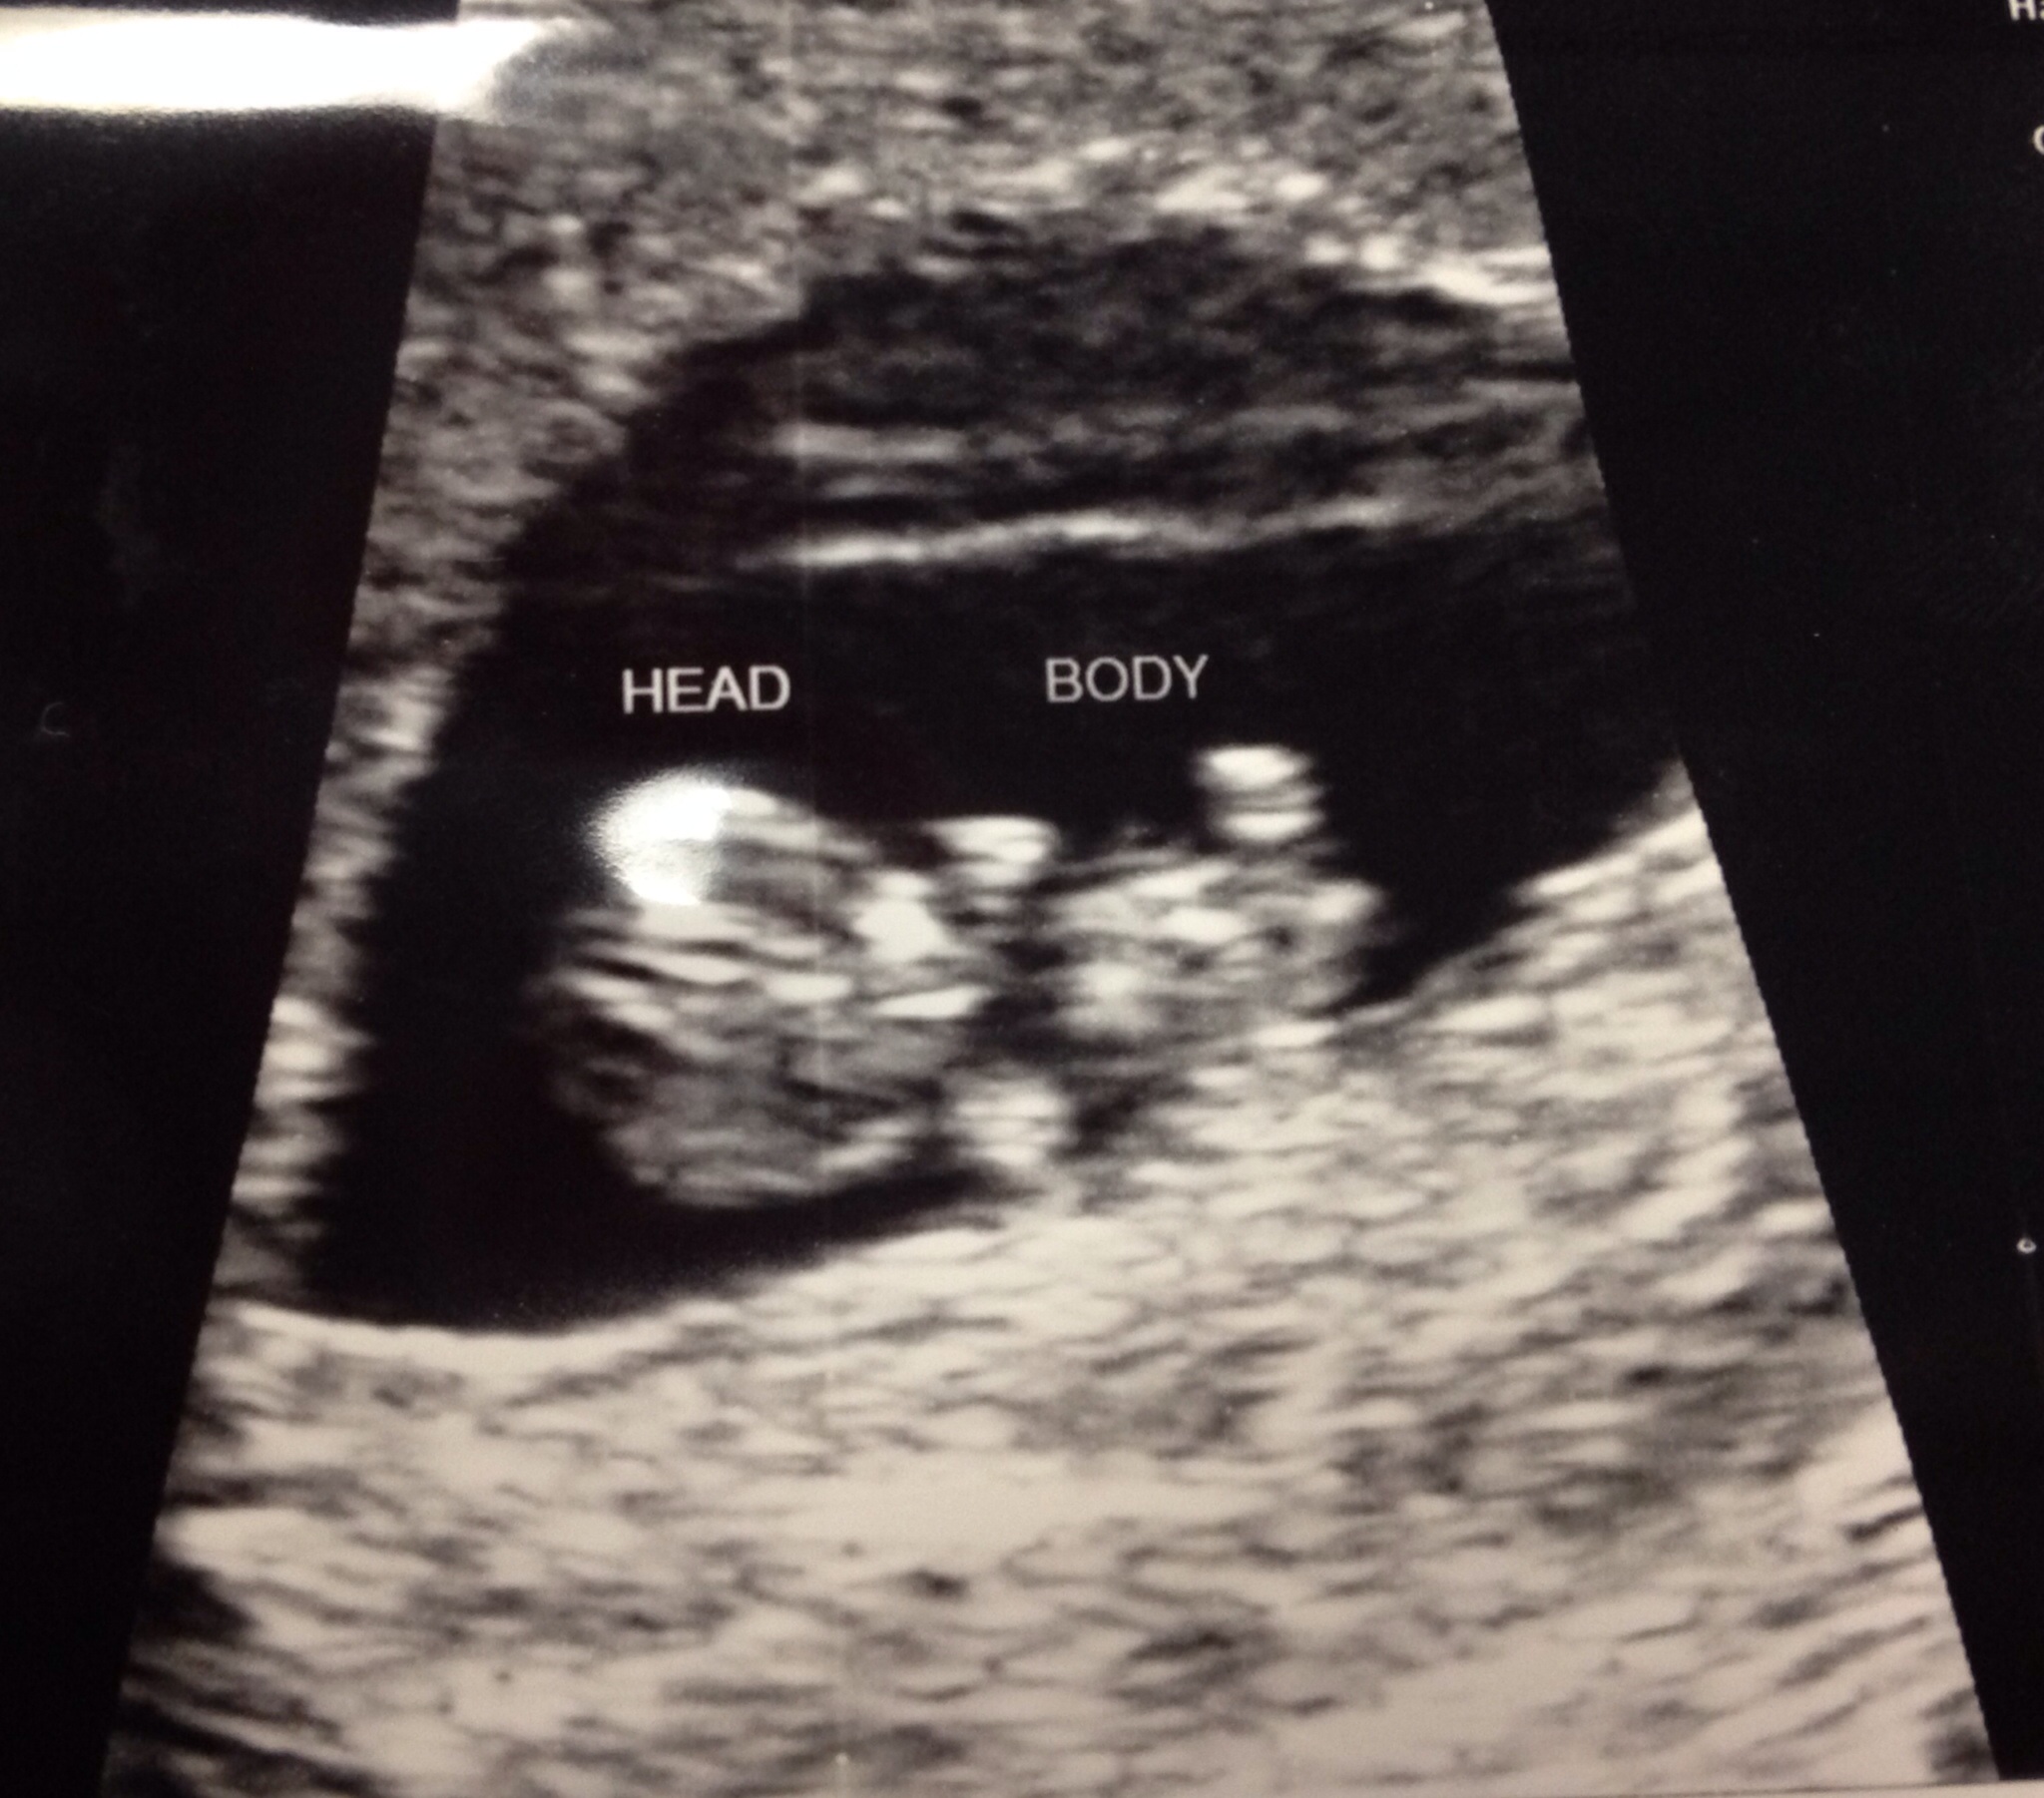

Thanks for all the well wishes!! Meet Baby M, measuring right on track with a strong heartbeat of 162! The little guy/girl was dancing for us and wiggling all around, and I fell in love! My H said it hit him that he is gonna be a dad. I'm so relieved and I feel like a brick wall has been lifted.

Thanks for all the well wishes. My appointment was amazing. They decided to do another ultrasound. It actually looks like a baby now with a nice strong heartbeat.